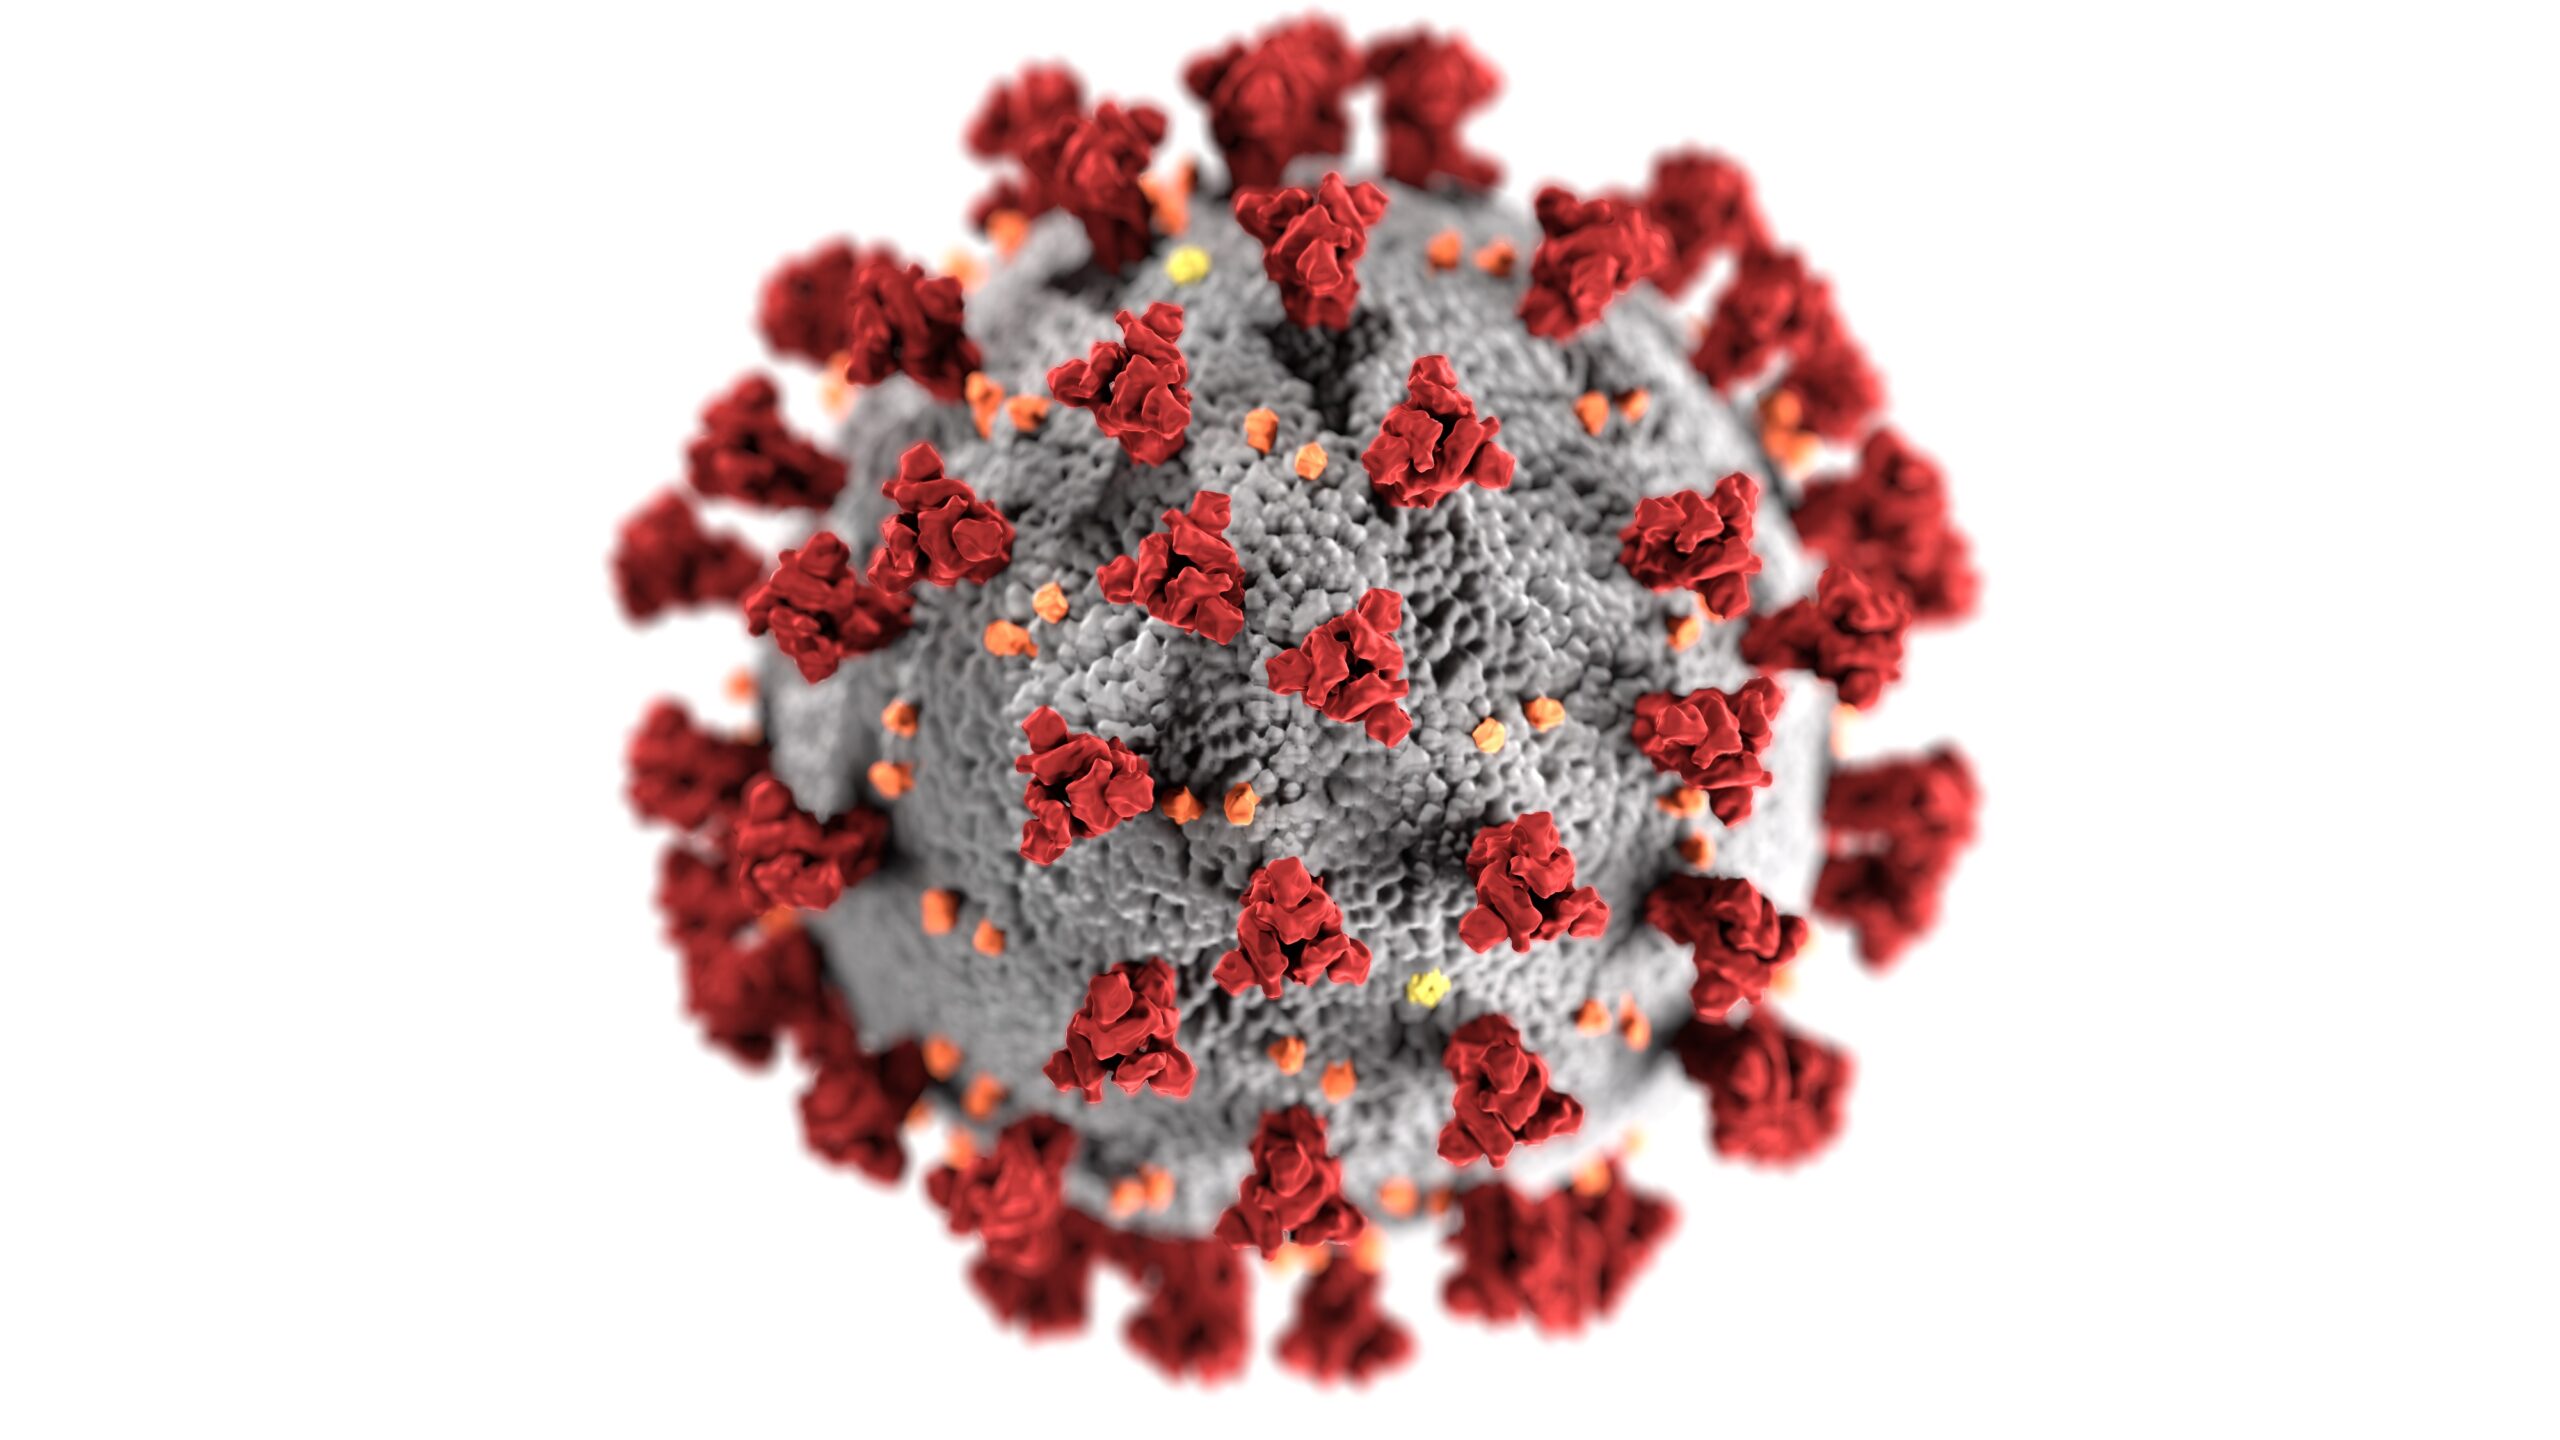

In questo recentissimo lavoro (dic 2021), Zuo e colleghi hanno caratterizzato il microbiota intestinale di

Il ruolo fondamentale del microbiota intestinale nel mantenere l’omeostasi immunitaria è ormai una certezza. Anche

È noto che un microbiota intestinale in salute permette di mantenere l’omeostasi del sistema immunitario,